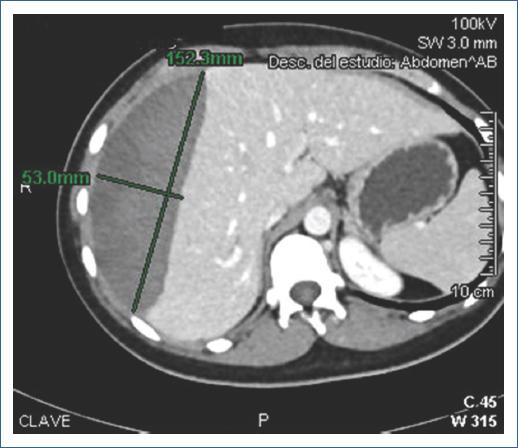

Paciente de sexo femenino de 47 años, sin antecedentes relevantes. Con diagnóstico por ultrasonido de coledocolitiasis, se realizó CPRE programada. Procedimiento a cargo del médico adscrito, asistido por residente; tiempo de canulación: 3 minutos, con dos intentos. Se realizó esfinterotomía, identificación de defecto de llenado, barrido con balón y colocación de endoprótesis biliar. Posteriormente presentó dolor epigástrico intenso. Laboratorios: Hb 8.1, BT 2.16, BD 0.12, BI 2.04; AST 110, ALT 45, FA 115, GGT 95, DHL 126, amilasa 86, lipasa 67. La TC reveló hematoma subcapsular hepático de 1,250 ml (Fig. 4). Se colocó drenaje percutáneo, con gasto inicial de 900 ml y gasto diario de 50 ml. Egresó a los 13 días, con resolución clínica y programación para colecistectomía laparoscópica.

Caso 5